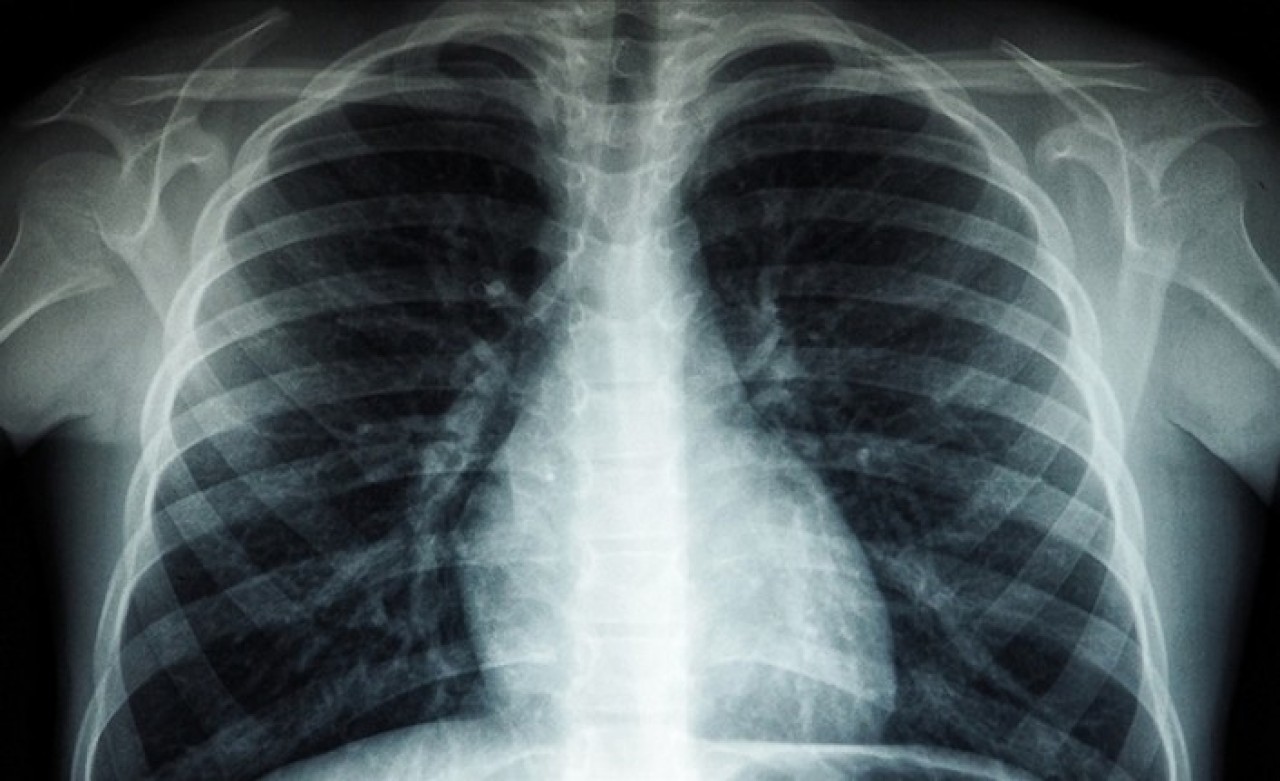

Röntgen ve ileri tetkiklerle hastalığın tespit edilebildiğinin altını çizen Özkara, Türkiye'de veremin 6 ay kullanılan ilaçlarla kolaylıkla tedavi edilebildiğine ve tüm tedavi masraflarının da devlet tarafından karşılandığına dikkati çekti.